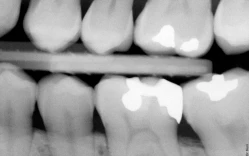

Hình 1: Chu vi chân răng có những điểm lồi lõm nên khi hướng tia X-quang đi qua sẽ tạo hình ảnh thấu quang ở vị trí ranh giới thân – chân.

Hình 2: Các vùng thấu quang cổ răng trên nhiều răng cùng một góc độ chụp và cường độ tia. Chú ý vùng thấu quang ở vị trí nghi vấn dưới mối hàn xoang II Black (hình trái). Chẩn đoán phân biệt bằng triệu chứng và đánh giá độ tụt lợi.